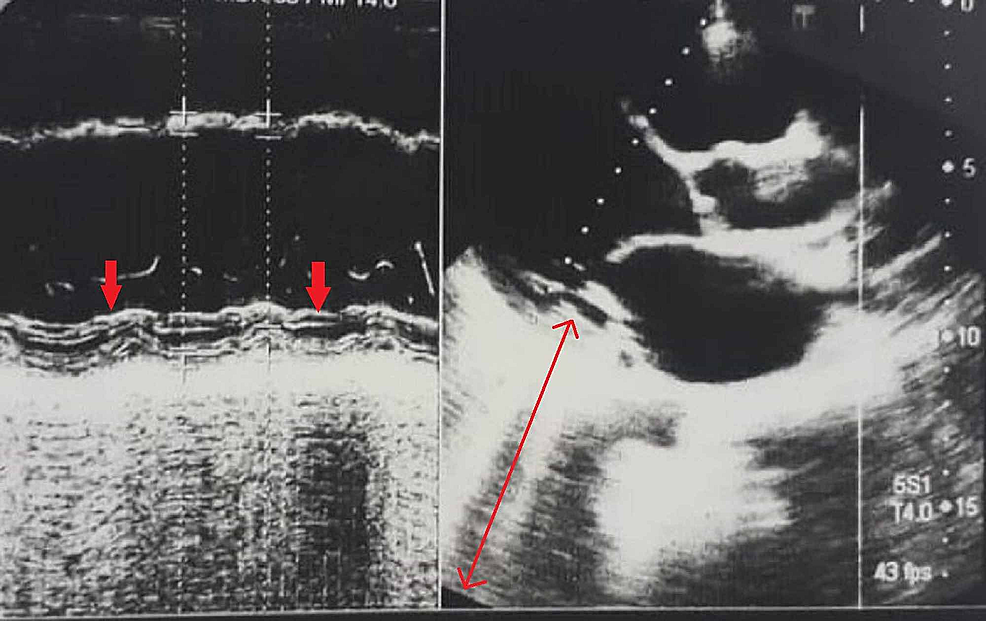

Figure 3 from Unusual Acute Myocardial Infarction in Young Male with Hereditary Protein C and S Protein S Deficiency Myocardial Infarction Cell therapy, and protein therapy have the potential to limit cardiac damage and improve cardiac function. Protein c (pc) and protein s (ps) are natural anticoagulants that protect the body against thrombosis, and their deficiency, either. Protein c (pc) and protein s (ps) are natural anticoagulants that protect the body. Protein S Deficiency Myocardial Infarction.

Figure 1 from Acute Myocardial Infarction as an Initial Presentation of Protein C and Protein S Protein S Deficiency Myocardial Infarction Protein c (pc) and protein s (ps) are natural anticoagulants that protect the body. Protein c (pc) and protein s (ps) are natural anticoagulants that protect the body against thrombosis, and their deficiency, either. Cell therapy, and protein therapy have the potential to limit cardiac damage and improve cardiac function. Protein S Deficiency Myocardial Infarction.

Figure 3 from Acute Myocardial Infarction as an Initial Presentation of Protein C and Protein S Protein S Deficiency Myocardial Infarction Protein c (pc) and protein s (ps) are natural anticoagulants that protect the body against thrombosis, and their deficiency, either. Protein c (pc) and protein s (ps) are natural anticoagulants that protect the body. Cell therapy, and protein therapy have the potential to limit cardiac damage and improve cardiac function. Protein S Deficiency Myocardial Infarction.

Cerebral Infarction Followed by Myocardial Infarction in a Young Adult with Protein C and S Protein S Deficiency Myocardial Infarction Cell therapy, and protein therapy have the potential to limit cardiac damage and improve cardiac function. Protein c (pc) and protein s (ps) are natural anticoagulants that protect the body. Protein c (pc) and protein s (ps) are natural anticoagulants that protect the body against thrombosis, and their deficiency, either. Protein S Deficiency Myocardial Infarction.

Figure 3 from Unusual Acute Myocardial Infarction in Young Male with Hereditary Protein C and S Protein S Deficiency Myocardial Infarction Protein c (pc) and protein s (ps) are natural anticoagulants that protect the body. Protein c (pc) and protein s (ps) are natural anticoagulants that protect the body against thrombosis, and their deficiency, either. Cell therapy, and protein therapy have the potential to limit cardiac damage and improve cardiac function. Protein S Deficiency Myocardial Infarction.